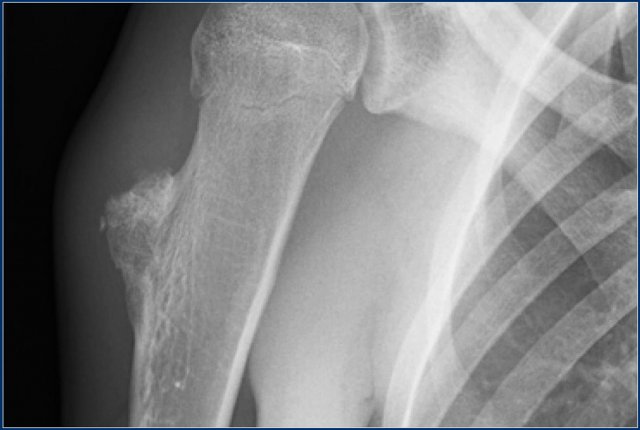

Here images of a 30-year-old male.

There is a wel-defined lytic lesion of the olecranon with several ridges and a pathologic fracture.

The differential diagnosis includes giant cell tumor and ABC.

The T2WI+FS shows fluid-levels due to sedimentation making ABC the most likely diagnosis.

Biopsy however revealed Brown tumor.